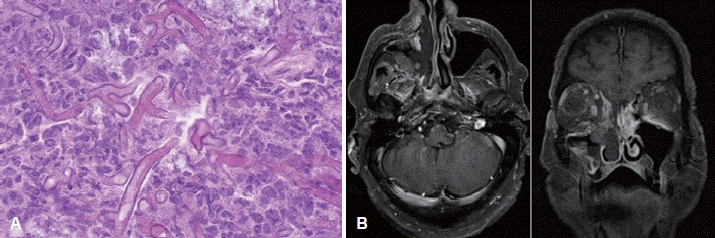

문 4. 58세 남성 환자가 3일 전부터 시작된 심한 우측 안면 통증, 비폐색, 시력 저하를 주소로 내원하였다. 환자는 10년 전 제2형 당뇨병 진단을 받았으나 혈당 조절이 불량한 상태였다. 비내시경 검사상 좌측 중비갑개와 비중격 점막 일부에서 검은색의 괴사 조직(necrotic lesion)이 관찰되었으며 조직검사 결과는 A와 같으며 MRI 검사 결과는 B와 같다. 이 환자의 가장 적절한 치료 원칙은 무엇인가?

문 4. 답 ③

해 설 이 환자는 잘 조절되지 않는 당뇨병이라는 AIFRS의 주요 위험 인자를 가지고 있으며, 증상, 검사결과상 Mucormycosis의 소견이다.

1) Mucormycosis 1차 약물: Mucormycosis는 voriconazole에 대한 선천적 내성을 나타내므로, 1차 치료제로는 L-AmB가 권장된다. ①번의 voriconazole은 부적절하다.

2) 치료 원칙: AIFRS의 치료는 강력한 항진균제 요법과 감염 부위의 괴사 조직을 적극적으로 제거하는 수술적 절제가 반드시 병행되어야 한다.